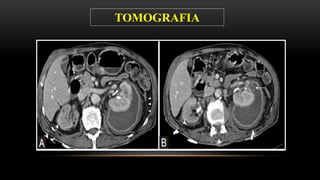

Se solicita el día 15/04/2015………TEM ABDOMINAL CON CONTRASTE

 RIÑON DERECHO: disminuido de tamaño, mide 7 cm, muestra parénquima adelgazado( laminar)

y con calcificaciones, tenue captación de contraste, no lesiones solidas ni quísticas, no litiasis

cálcica, los sistemas colectores dilatados, no hay excreción de sustancia de contraste

 RIÑON IZQUIERDO: localización y tamaño normal, con dilatación de grupos caliciales, se observa

menor captación de contraste, disminución de la diferenciación corticomedular, retardo en la

excreción dela sustancia de contraste, uréter izquierdo visualizado no dilatado, no litiasis.

 VEJIGA: pequeña, no litiasis, engrosamiento irregular de la mucosa.

 No adenopatías retroperitoneales

SE CONCLUYE:

 SIGNOS TOMOGRAFICOS QUE ESTAN EN RELACION CON PIELONEFRITIS CRONICA

IZQUIERDA. CONSIDERAR ORIGEN BACTERIANO, TBC entre otras

 EXCLUSION RENAL DERECHA.

 SIGNOS PATOLOGIA INFLAMATORIA VESICAL

TOMOGRAFIA

CALICES DILATADOS

CORTEZA ADELGAZADA